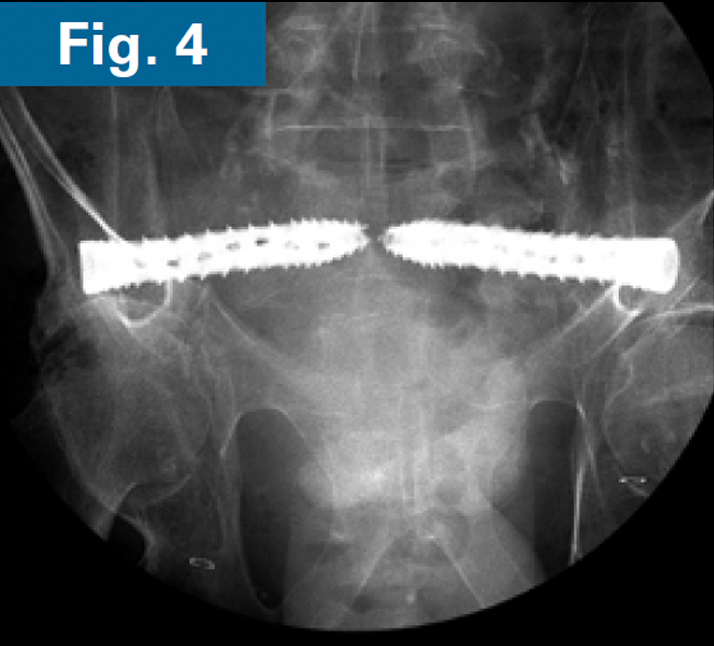

His pelvic abscesses were debrided and washed (lateral window) and antibiotic beads were placed followed by percutaneous placement of bilateral ilio-sacral style S1 implants. Intraoperative CT scan was performed after placement of 3.2 mm guidewires to confirm safe path of placement for iFuse TORQ implants in the setting of poor visualization of the foramen (Fig. 3). Bilateral 13.5mm iFuse TORQ implants were placed and the patient was allowed weightbearing as tolerated for activities of daily living at his home (Fig. 4).

• Immediate postoperative CT scan demonstrate safe placement of implants (Figs. 5A and 5B).

• AP and standing lateral sacral view at 3 months follow-up.

• Callous formation noted on the lateral radiograph (Figs. 6A and 6B).

• Clinically, the patient is ambulating comfortably and is not requiring opioids.4